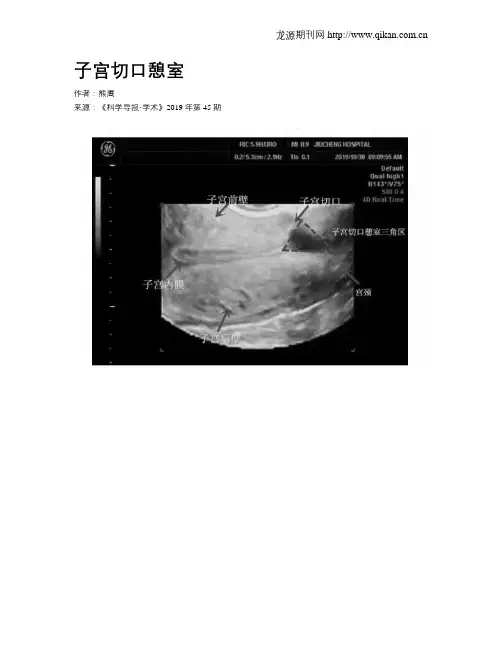

子宫切口憩室作者:熊鹰来源:《科学导报·学术》2019年第45期子宫切口憩室的概念:子宫切口憩室是指子宫下段剖宫产术后子宫切口部位由于愈合缺陷出现的突向浆膜层的一个凹陷,与后壁内膜线形成一个三角形的区域,是宫腔内多出来的一个空间,里面有或少许内膜组织。

例如下图:三角形区域。

超声检查是最常用、又快捷、非创伤和廉价的诊断方式,超声图像主要提示,子宫前壁下段剖宫产切口可见宫腔内凸向肌层或浆膜层的三角形液性暗区。